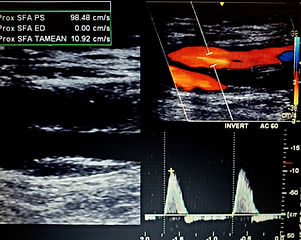

Lower Arterial Duplex

Upper Arterial Duplex

Lower Arterial Duplex evaluate for Peripheral Arterial Disease (PAD) is a common circulation problem in which the arteries that carry blood to the legs or arms become narrowed or clogged.

"Did you know, P.A.D. affects 8 to 12 million people in the United States, especially those over 50 with or without Smoking history, High Blood Pressure and or Diabetes"